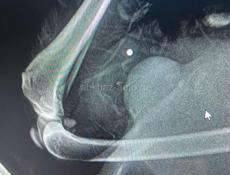

Помощь собаке 🙏

Дополнительная информация: https://chat.whatsapp.com/CPJrkdCqUGg8WK3iQZBeYd?mode=gi_t Вступайте в группу помощи Антошке из Абхазии. Ему предстоит операция,без которой Антошка будет инвалидом. Нам предстоит операция на позвоночнике и удаление пуль из тела. Сбор только на операцию - почти 80000 руб.. Просим помощи для Антошки...❤️🙏❤️🙏❤️🙏❤️ Карта помощи : 5536914116400338 - Тинькофф Кирса Ребекка Сергеевна PayPal: tomborn63@online.de ЛЮБАЯ СУММА , ДАЖЕ 100₽ ♥️ ЗАХОДИТЕ В ГРУППУ, ТАМ ВСЕ ОБ АНТОШКЕ